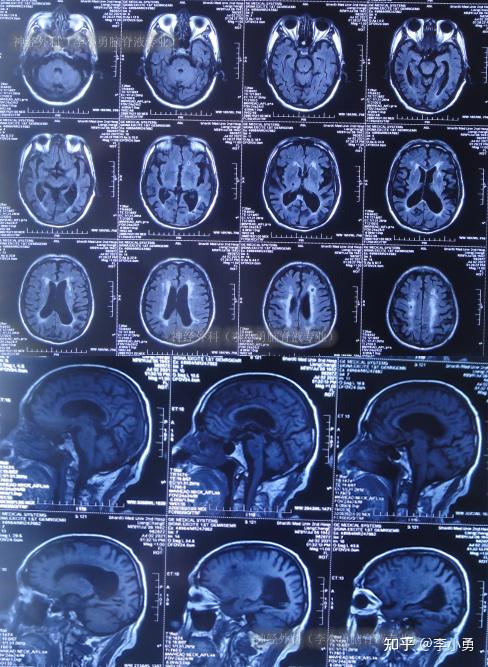

老年正常压力脑积水首次腰大池分流术失败并颅内出血手术,仍脑积水

老年正常压力脑积水首次腰大池分流术失败并颅内出血手术后,在多方